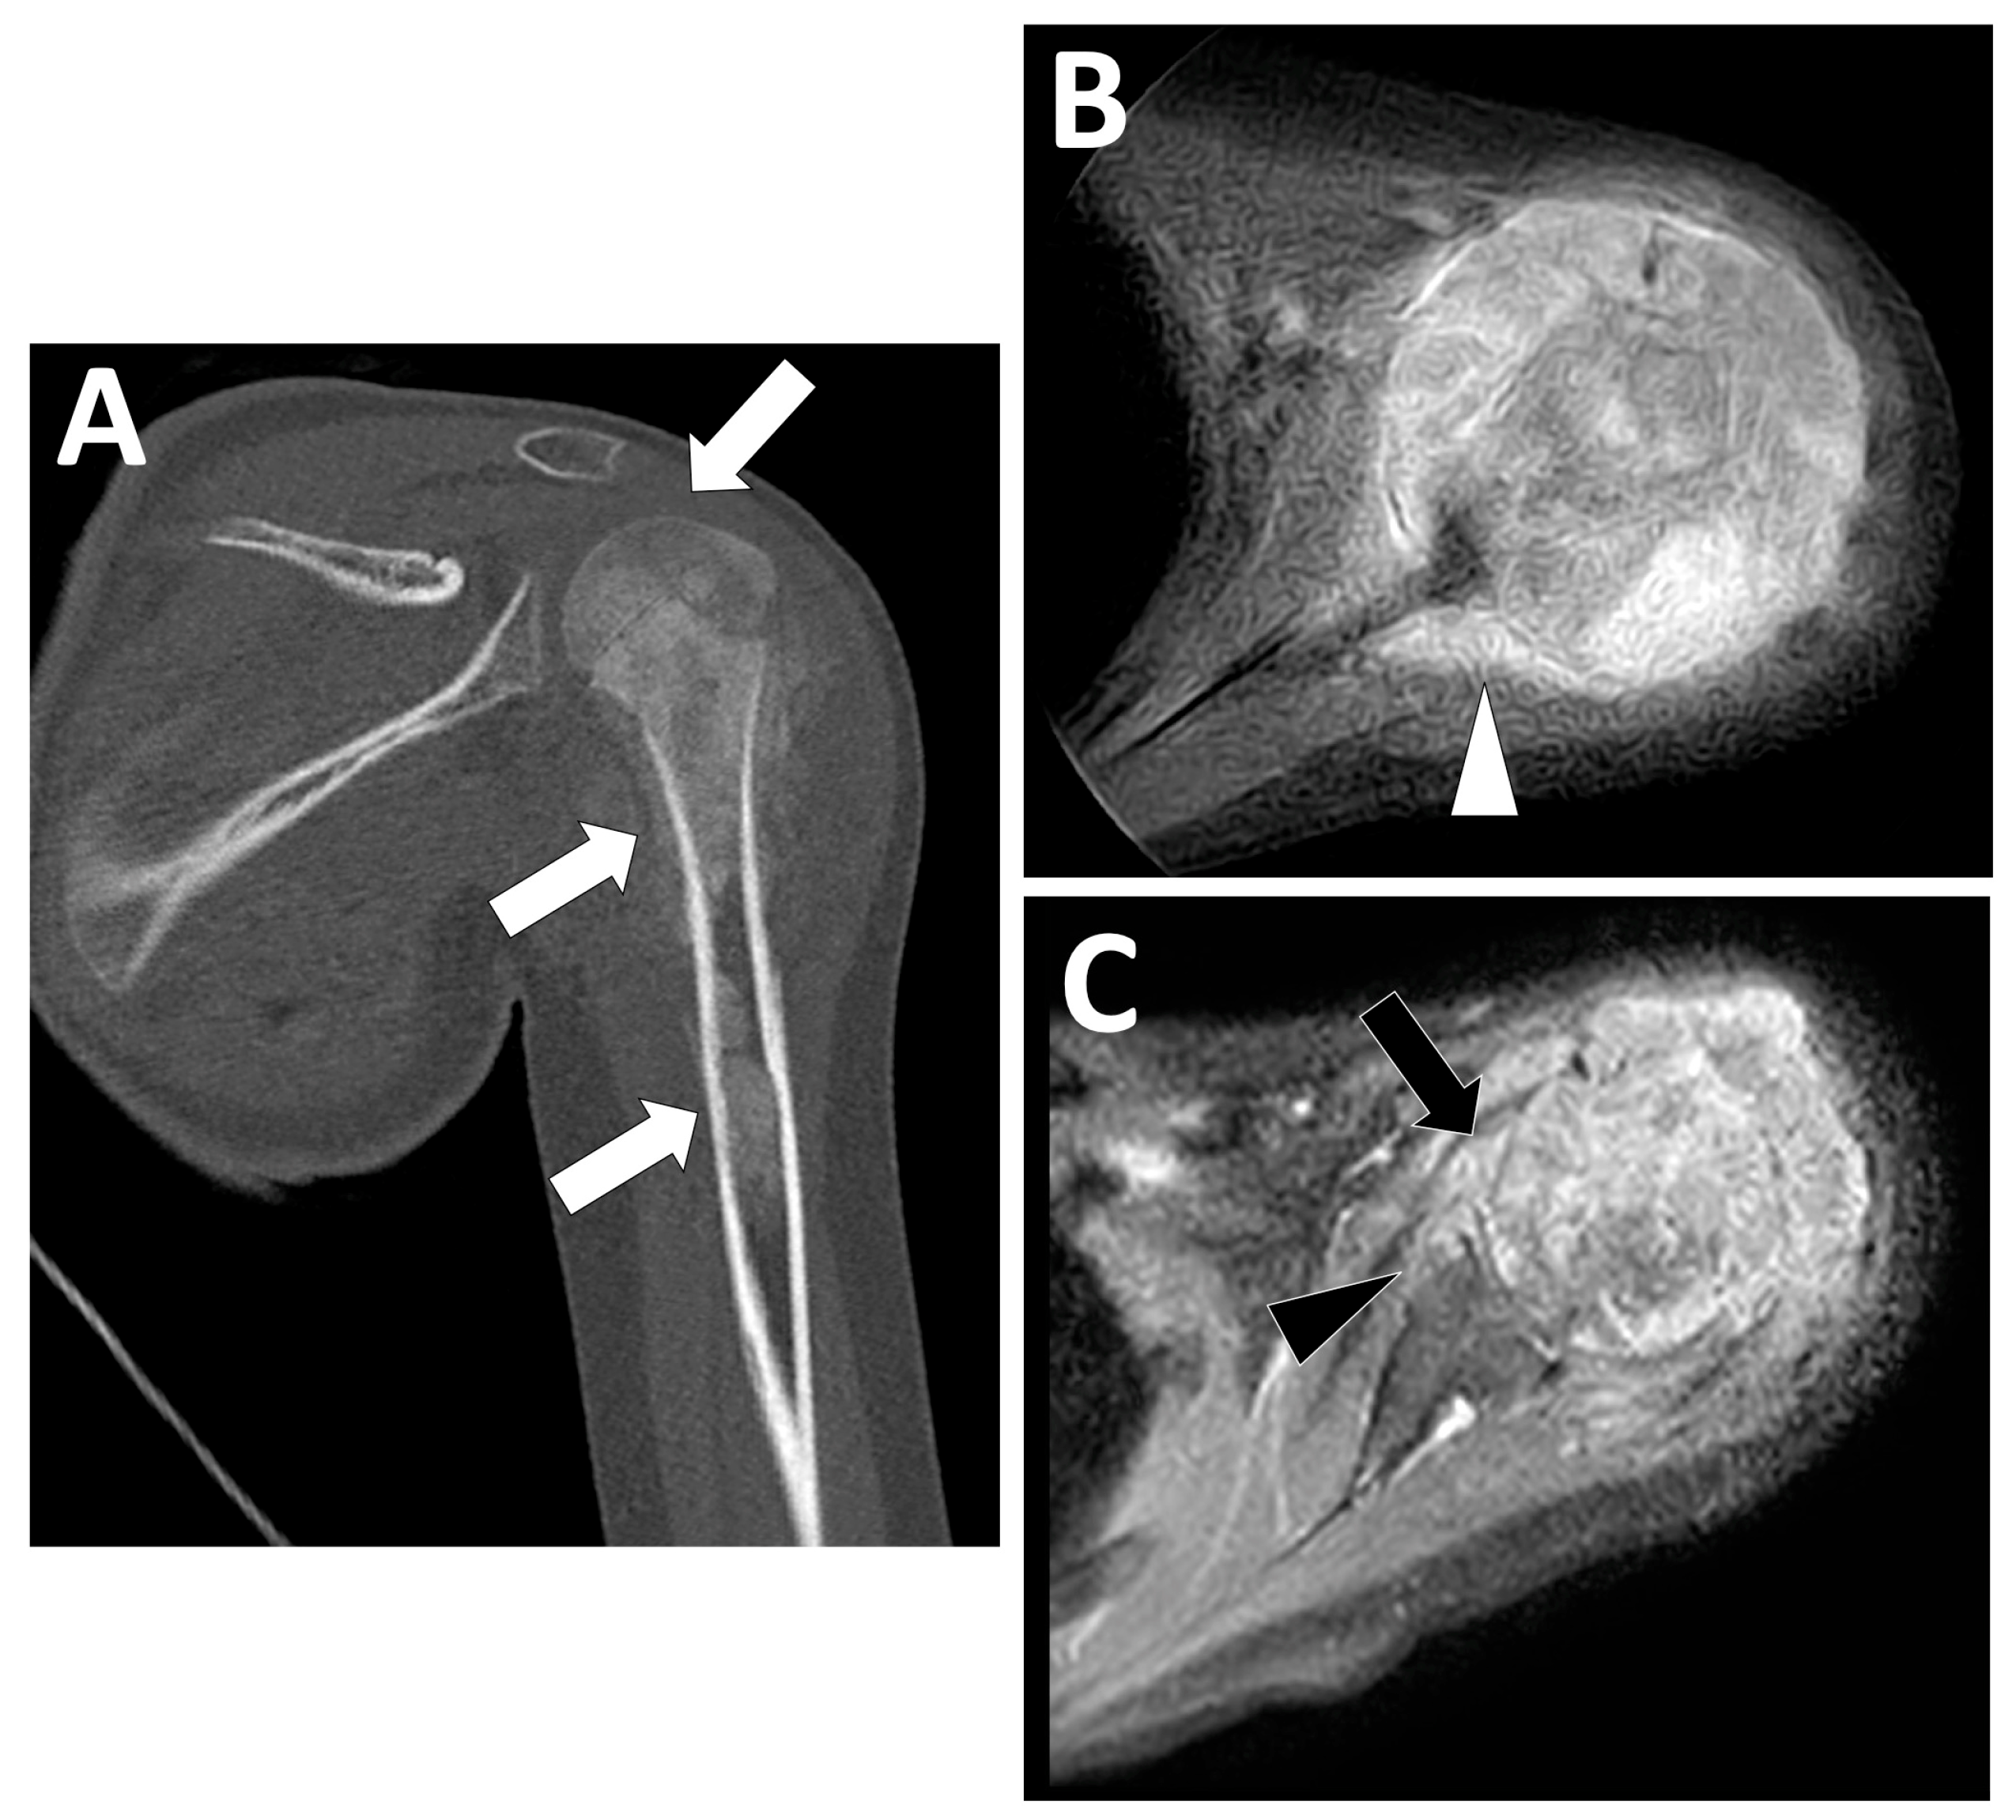

2.3. Radiological Findings on CT

2.4. Radiological Findings on MRI